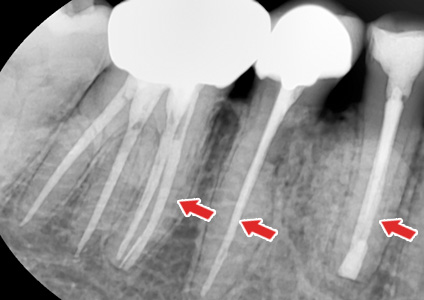

½Å°æÄ¡·á¸¦ ÇÑ Ä¡¾ÆÀÇ X-ray »çÁø

½Å°æÄ¡·á°¡ ÇÊ¿äÇÑ °æ¿ì